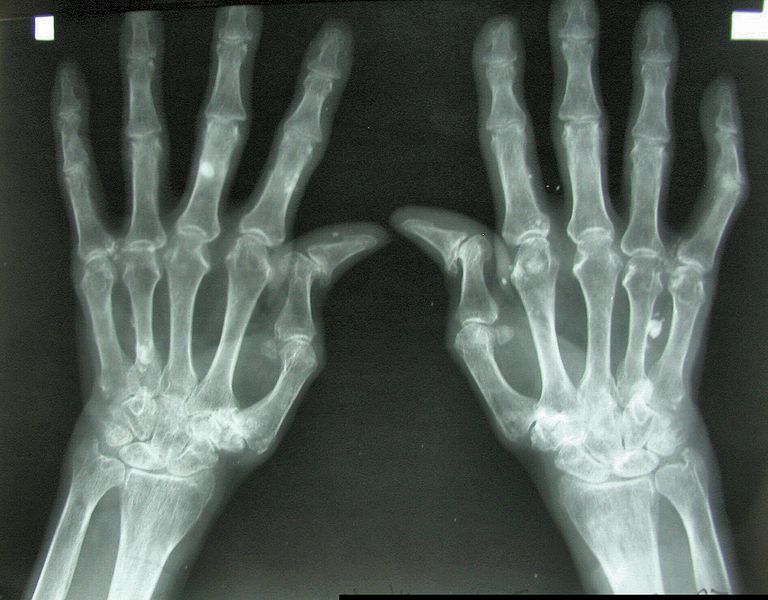

Amerykańscy pacjenci z RZA odstawiają leki biologiczne

Połowa z amerykańskich pacjentów, którzy podjęli leczenie reumatoidalnego zapalenia stawów (RZA) lekami biologicznymi – odstawiło je w ciągu dwóch lat stosowania – wynika z amerykańskich danych rejestrowych. Najczęściej podawanym przez pacjentów powodem odstawienia leku był „brak skuteczności”.